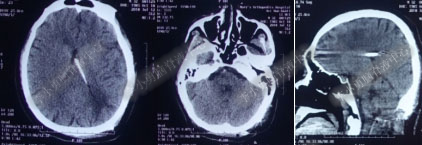

术后7天(2016年5月18日),症状有所缓解,复查头部MRI(图-2)幕上脑室较术前缩小,但是“四脑室仍扩张”,医生认为 “正常”于术后8天(2016年5月19日)出院。

图-2:2016年5月18日头部MRI

图-3:2016年9月26日头部MRI

第1次内镜术后330余天即11个月(2017年4月),又开始出现头晕症状并逐渐加重。2017年6月13日(第1次内镜术后367天),行头部MRI(图-4)检查显示全脑室系统扩大。

图-4:2017年6月13日头部MRI